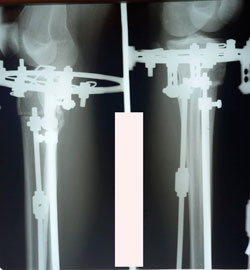

на фиксации